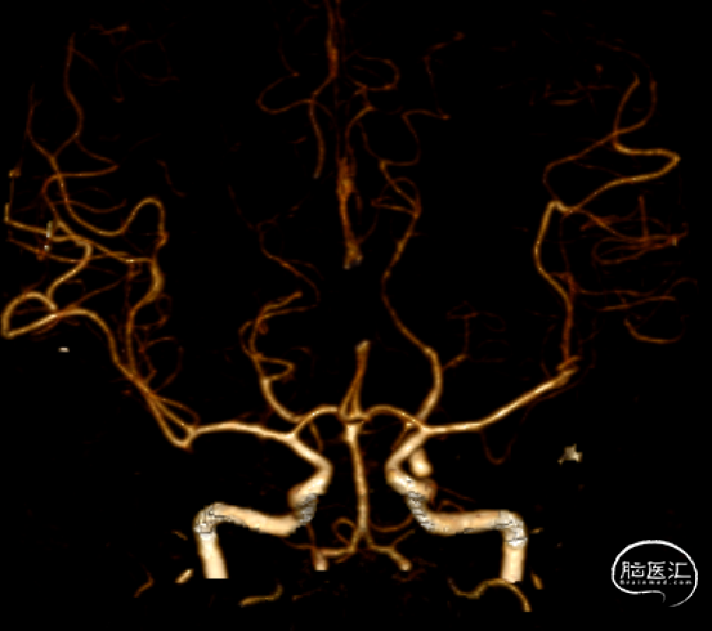

左侧颈内动脉C7段动脉瘤

左侧颈内动脉后交通段动脉瘤整体大小约4.9mm×9.3mm,

子瘤约4.3mm×2.4mm,

主瘤体5.8mm×4.1mm,

瘤颈宽3.0mm,不规则